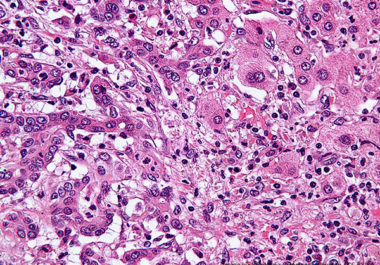

The FDA approved the use of a companion diagnostic to identify patients with tumors that have large numbers of...